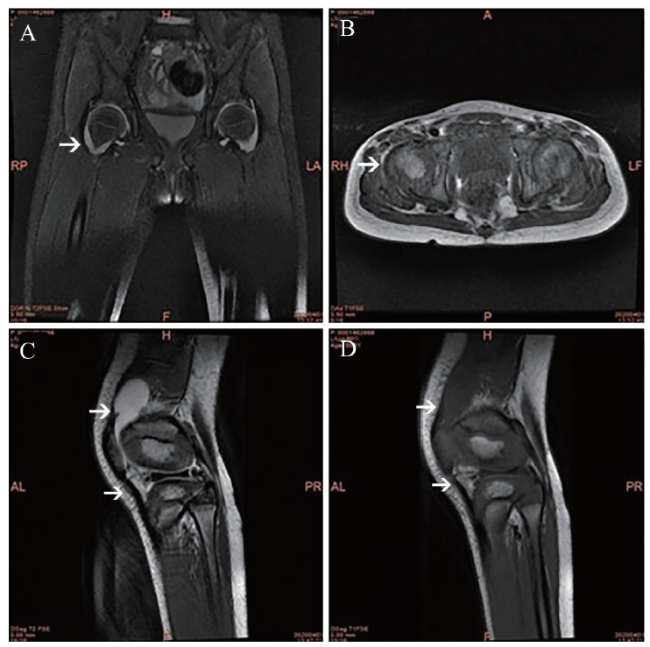

图2 例2丙种球蛋白非敏感型川崎病患儿大腿MRI

A:MRI示双侧大腿上段及下段后外侧肌肉水肿;B:双侧髋关节腔、双侧髌上囊、双侧膝长T2信号提示关节腔积液

例 2 患儿男,3岁,因发热和颈部肿痛4 d于2020年10月24日入我科。患儿起病以来偶有腹痛,呕吐胃内容物2次。在当地诊所静脉滴注头孢呋辛钠2 d,仍有发热。入院体格检查:体温39.0℃,心率140次/分。神志清晰,精神差,呼吸略促。全身散在红色皮疹,无抓痕。卡疤无发红。双侧颈部触及肿大淋巴结,左侧明显,部分融合,最大约5.0 cm×3.0 cm,质韧,皮温不高,有触痛,表面无破溃。双侧球结膜略充血、见少许白色分泌物。鼻翼无扇动,口唇干燥、无皲裂,口腔黏膜充血明显,轻度草莓舌,咽部充血。心、肺、腹无异常。肛周皮肤潮红、无脱皮。双足趾稍硬肿、无脱皮,双手末端无红肿、无膜状脱皮。病理征阴性。实验室检查:血红蛋白112 g/L,红细胞3.98×1012/L,白细胞 13.38×109/L,血小板491×109/L。CRP 62.07 mg/L,ESR 64 mm/h。白蛋白29 g/L,血清钠130.9 mmol/L。脑脊液有核细胞计数102×106/L。脑钠肽正常。IL-6 80.03 pg/ml。UCG显示冠状动脉左主干2.6 mm(Z值= 1.21)、右冠状动脉2.10 mm(Z值= 0.70)。标准12导联体表心电图正常。诊断为川崎病合并无菌性脑膜炎,给予大剂量丙种球蛋白(2 g/kg)和阿司匹林[30 mg/(kg·d)],并予甘露醇降颅压。经治疗后患儿皮疹及结膜充血消退,予第1剂丙种球蛋白治疗后36 h仍持续发热,考虑为丙种球蛋白非敏感型川崎病,继续予第2剂丙种球蛋白治疗后患儿转为低热,体温最高37.8℃。发病第9日,患儿出现颈部、双手指及双下肢疼痛,颈部活动受限,不能握持,不能独站及行走,双下肢肿胀,左下肢明显。复查血红蛋白103 g/L,白细胞 22.95×109/L,血小板586×109/L,CRP 88.98 mg/L。抗O阴性。RF、抗核抗体谱均阴性。MRI显示双侧大腿上段及下段后外侧肌肉水肿,双侧髋关节腔、双侧髌上囊、双侧膝关节腔积液(图2),提示合并严重关节炎。给予患儿口服泼尼松[起始量2mg/(kg·d)]治疗,给药后第2日患儿体温恢复正常。阿司匹林减为最小量维持[3 mg/(kg·d)]。患儿颈部、双手及双下肢疼痛逐渐减轻。复查MRI显示肌肉水肿减轻,关节腔积液明显减少。在恢复期患儿出现了指趾末梢脱皮。患儿情况稳定后出院,出院诊断:①丙种球蛋白非敏感型川崎病;②严重关节炎并关节腔积液;③无菌性脑膜炎;④低钠血症;⑤低蛋白血症。患儿出院后继续口服泼尼松,逐渐减停、疗程4周,继续口服小剂量阿司匹林。出院后2周、1个月接受随访,患儿颈部及肢体疼痛完全消失,复查MRI显示关节腔积液完全吸收。随访至出院2个月后,患儿情况稳定、无任何不适。